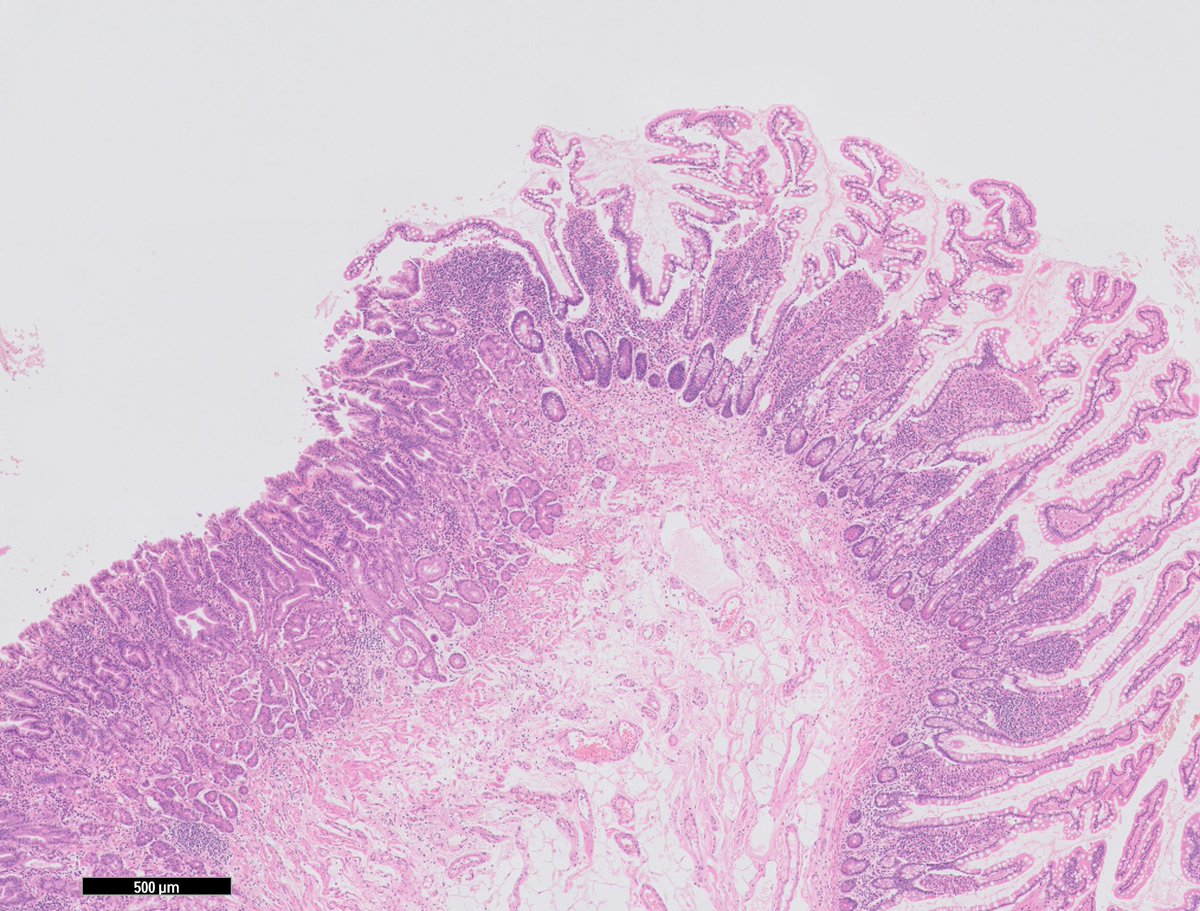

(1/4) Uterine Stromal Tumors #1: Low-Grade Endometrial Stromal Sarcoma (LG-ESS) • Gross appearance - “bag of worms” • Low-grade cellularity resembling proliferative endometrial stroma • Tongue-like invasion of myometrium • Frequent vascular invasion #GYNpath

(1/4) Uterine Stromal Tumors #1:

Low-Grade Endometrial Stromal Sarcoma (LG-ESS)

• Gross appearance - “bag of worms”

• Low-grade cellularity resembling proliferative endometrial stroma

• Tongue-like invasion of myometrium

• Frequent vascular invasion

#GYNpath